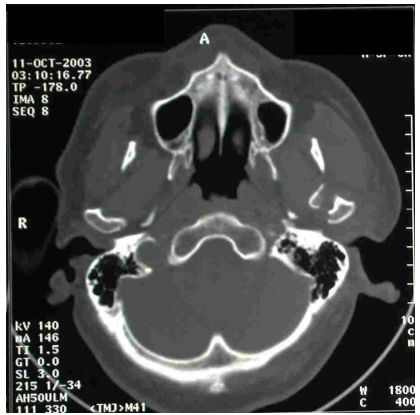

22. 下圖是頭部電腦斷層影像,其診斷應是: (A) 右側上顎骨骨折 (B) 右側下顎骨髁突(condylar process)骨折 (C) 左側上顎骨骨折 (D) 左側下顎骨髁突骨折